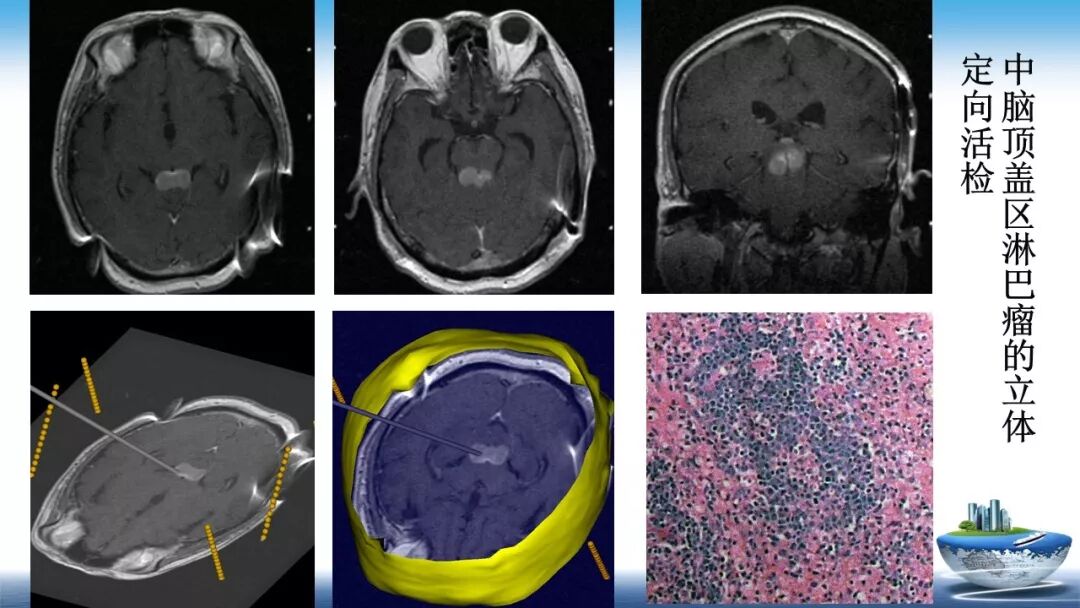

立体定向活检在脑干中线病变精准诊断中的作用

今天为大家带来的是中国人民解放军总医院第六医学中心(原中国人民解放军海军总医院)王亚明、于新、张剑宁带来的精彩课题分享:立体定向活检在脑干中线病变精准诊断中的作用,欢迎观看、阅读!